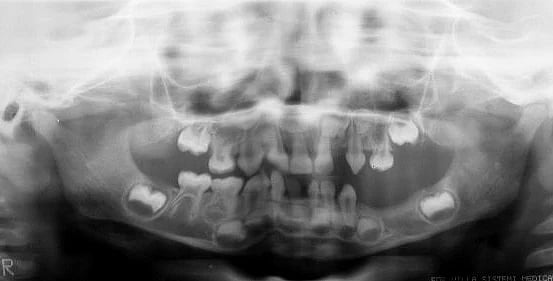

Dr. Graham, a professor of medical genetics and pediatrics, grew up with a rare dental condition seen in several members of his family across five generations. Many relatives were born with natal teeth, teeth present at birth that were fragile and fell out shortly afterward. In some cases, the adult teeth that would normally replace them never developed, a disorder known as tooth agenesis.

In Graham’s case, the natal teeth were described as thin and poorly formed, lacking proper root development, which caused them to fall out shortly after birth.

Natal teeth are uncommon but not extremely rare, occurring in roughly 1 in 1,000 newborns, though the combination of multiple natal teeth and missing permanent teeth seen in Graham’s family is far rarer.

The condition affected numerous family members, including Graham’s mother, siblings, children and even grandchildren. His mother wore dentures for much of her life, while Graham himself required extensive dental procedures and implants to manage the missing teeth.

The dental trait in the family appears to have been inherited in an autosomal dominant pattern and has been traced through approximately 150 years of family history beginning with Graham’s maternal grandfather.

Two of Graham’s three sons were also born with natal teeth, and one of his granddaughters has shown signs of the same condition.